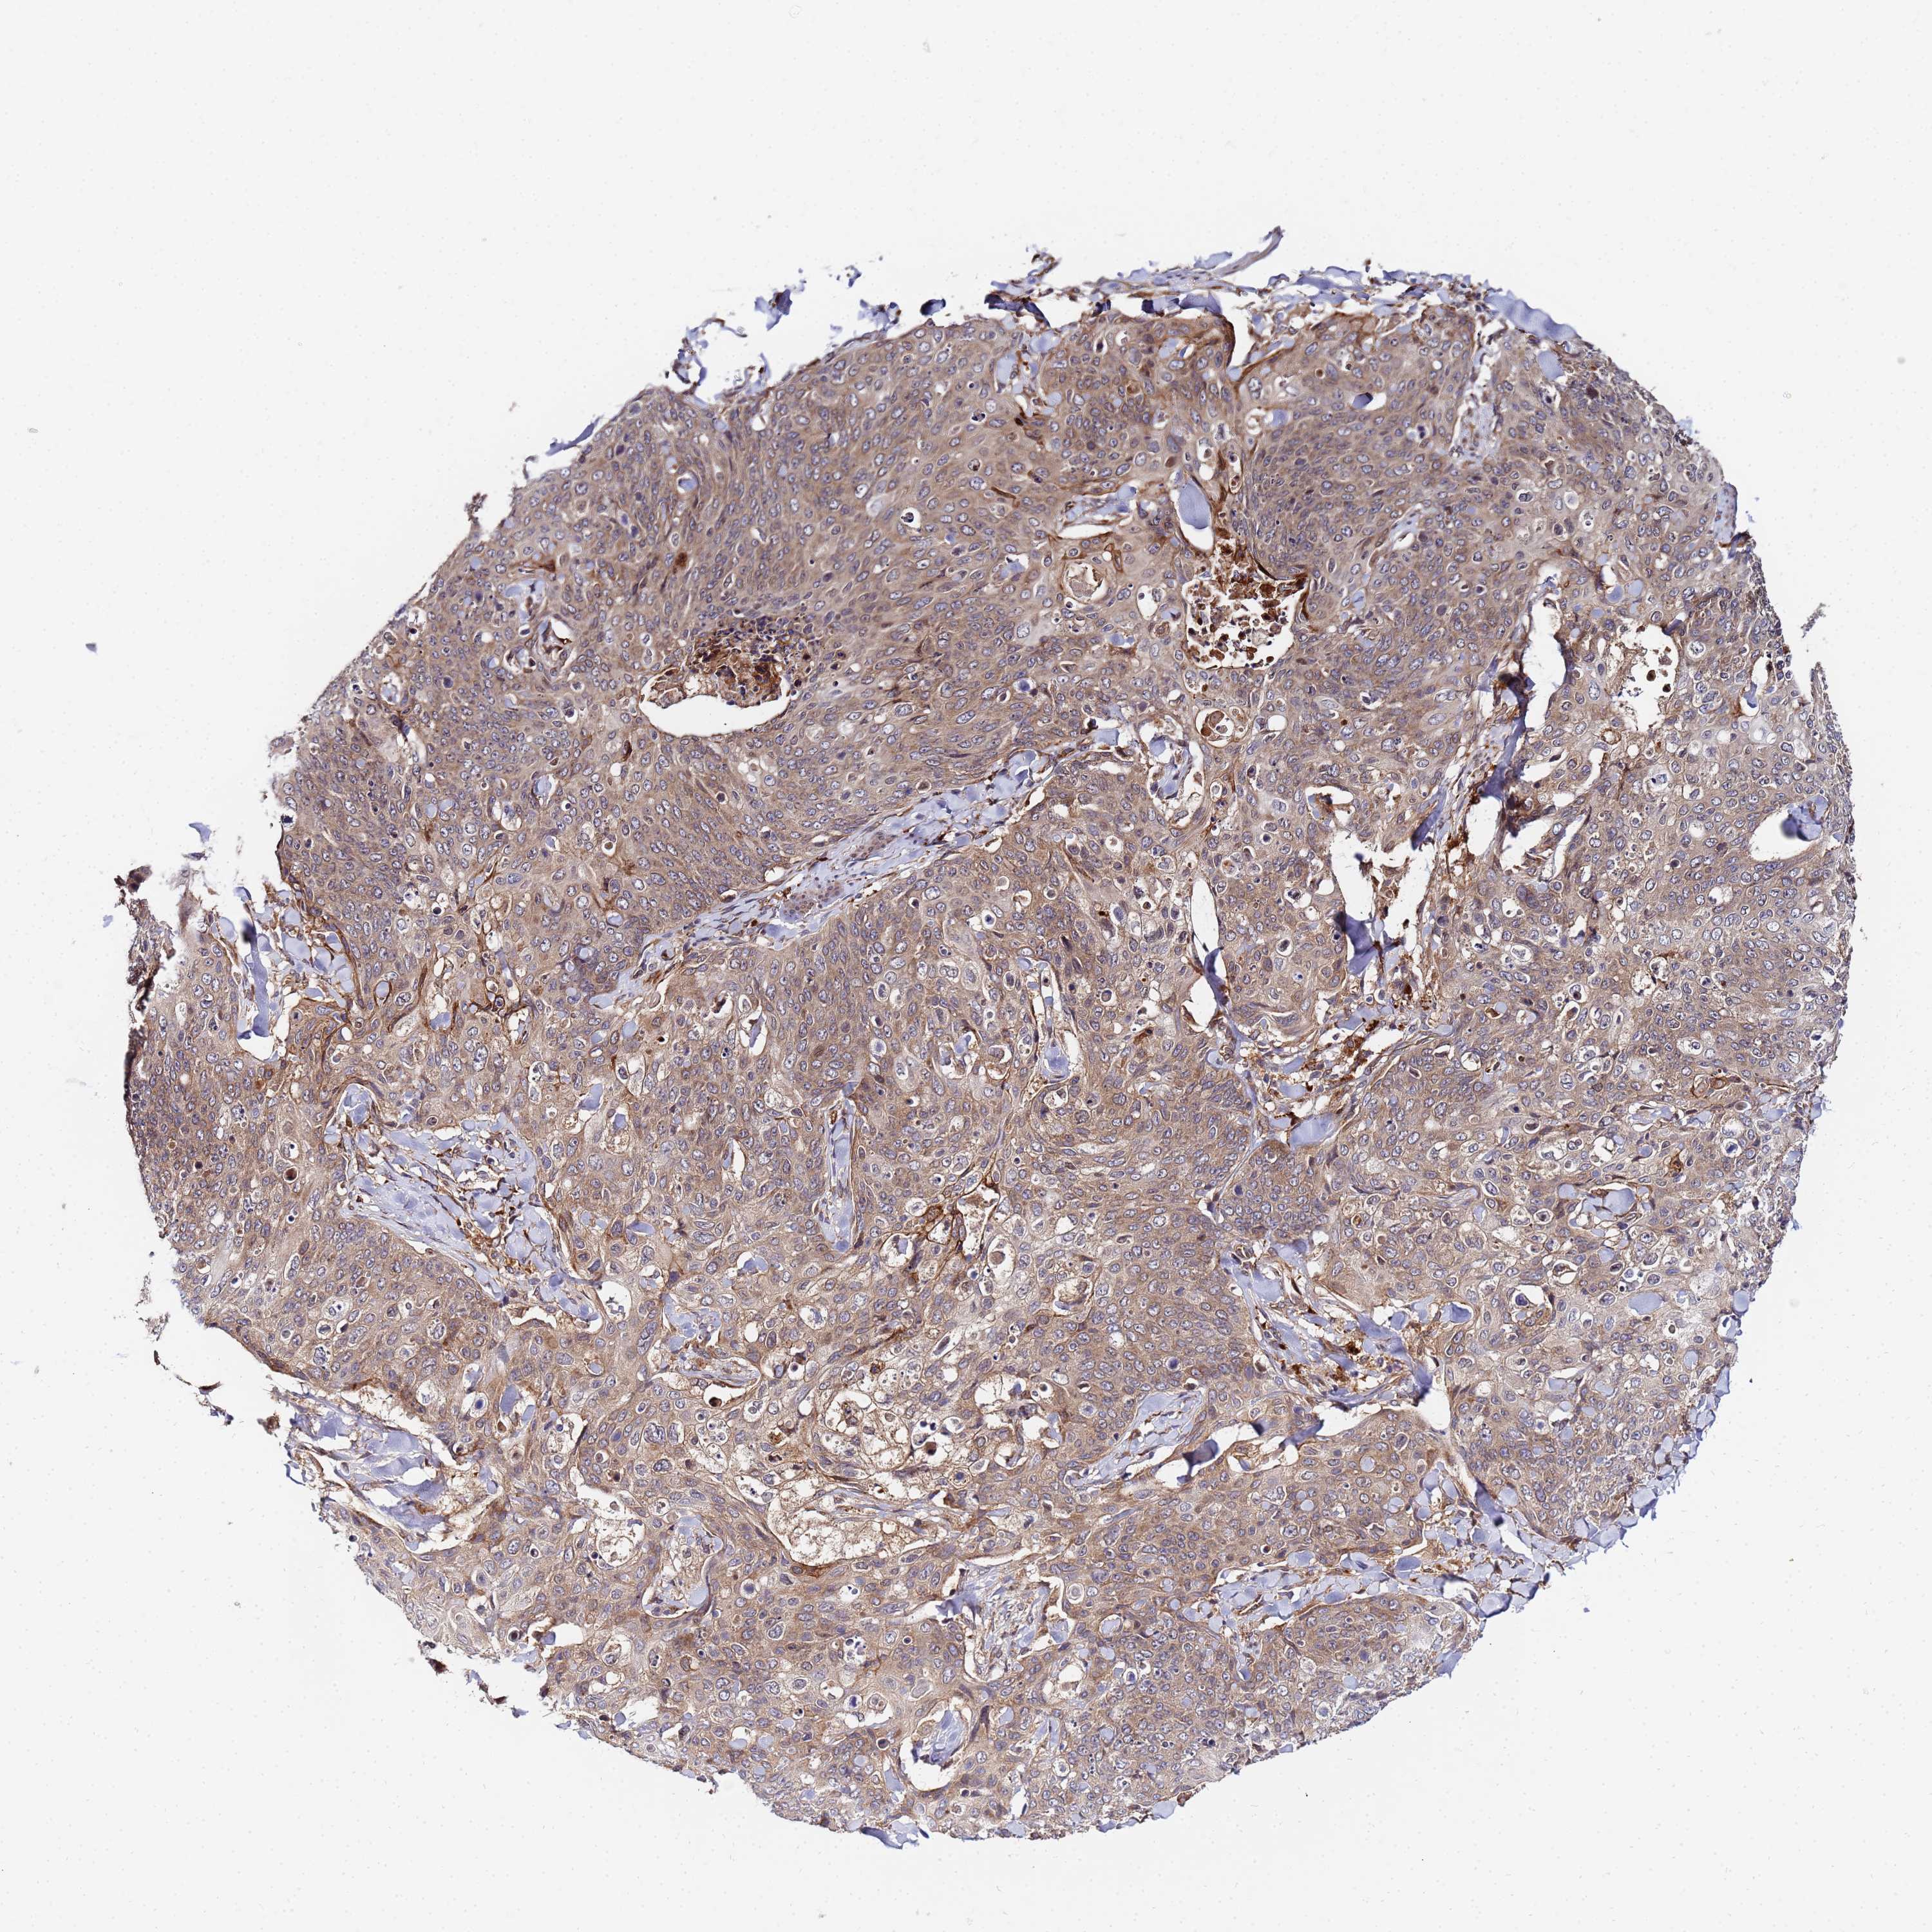

CANCER SKIN CANCER Show tissue menu

SKIN CANCER - Protein expressioni

A mouse-over function shows sample information and annotation data. Click on an image to view it in a full screen mode. Samples can be filtered based on level of antibody staining by selecting one or several of the following categories: high, medium, low and not detected. The assay and annotation is described here.

Each image is clickable and will lead to virtual microscopy that enables deeper exploration of all samples and also displays staining intensity scores, fraction scores and subcellular localization as well as patient and tissue information for each sample.

Antibody HPA038717

Antibody HPA042803

Basal cell carcinoma

Squamous cell carcinoma, NOS

Squamous cell carcinoma, metastatic, NOS